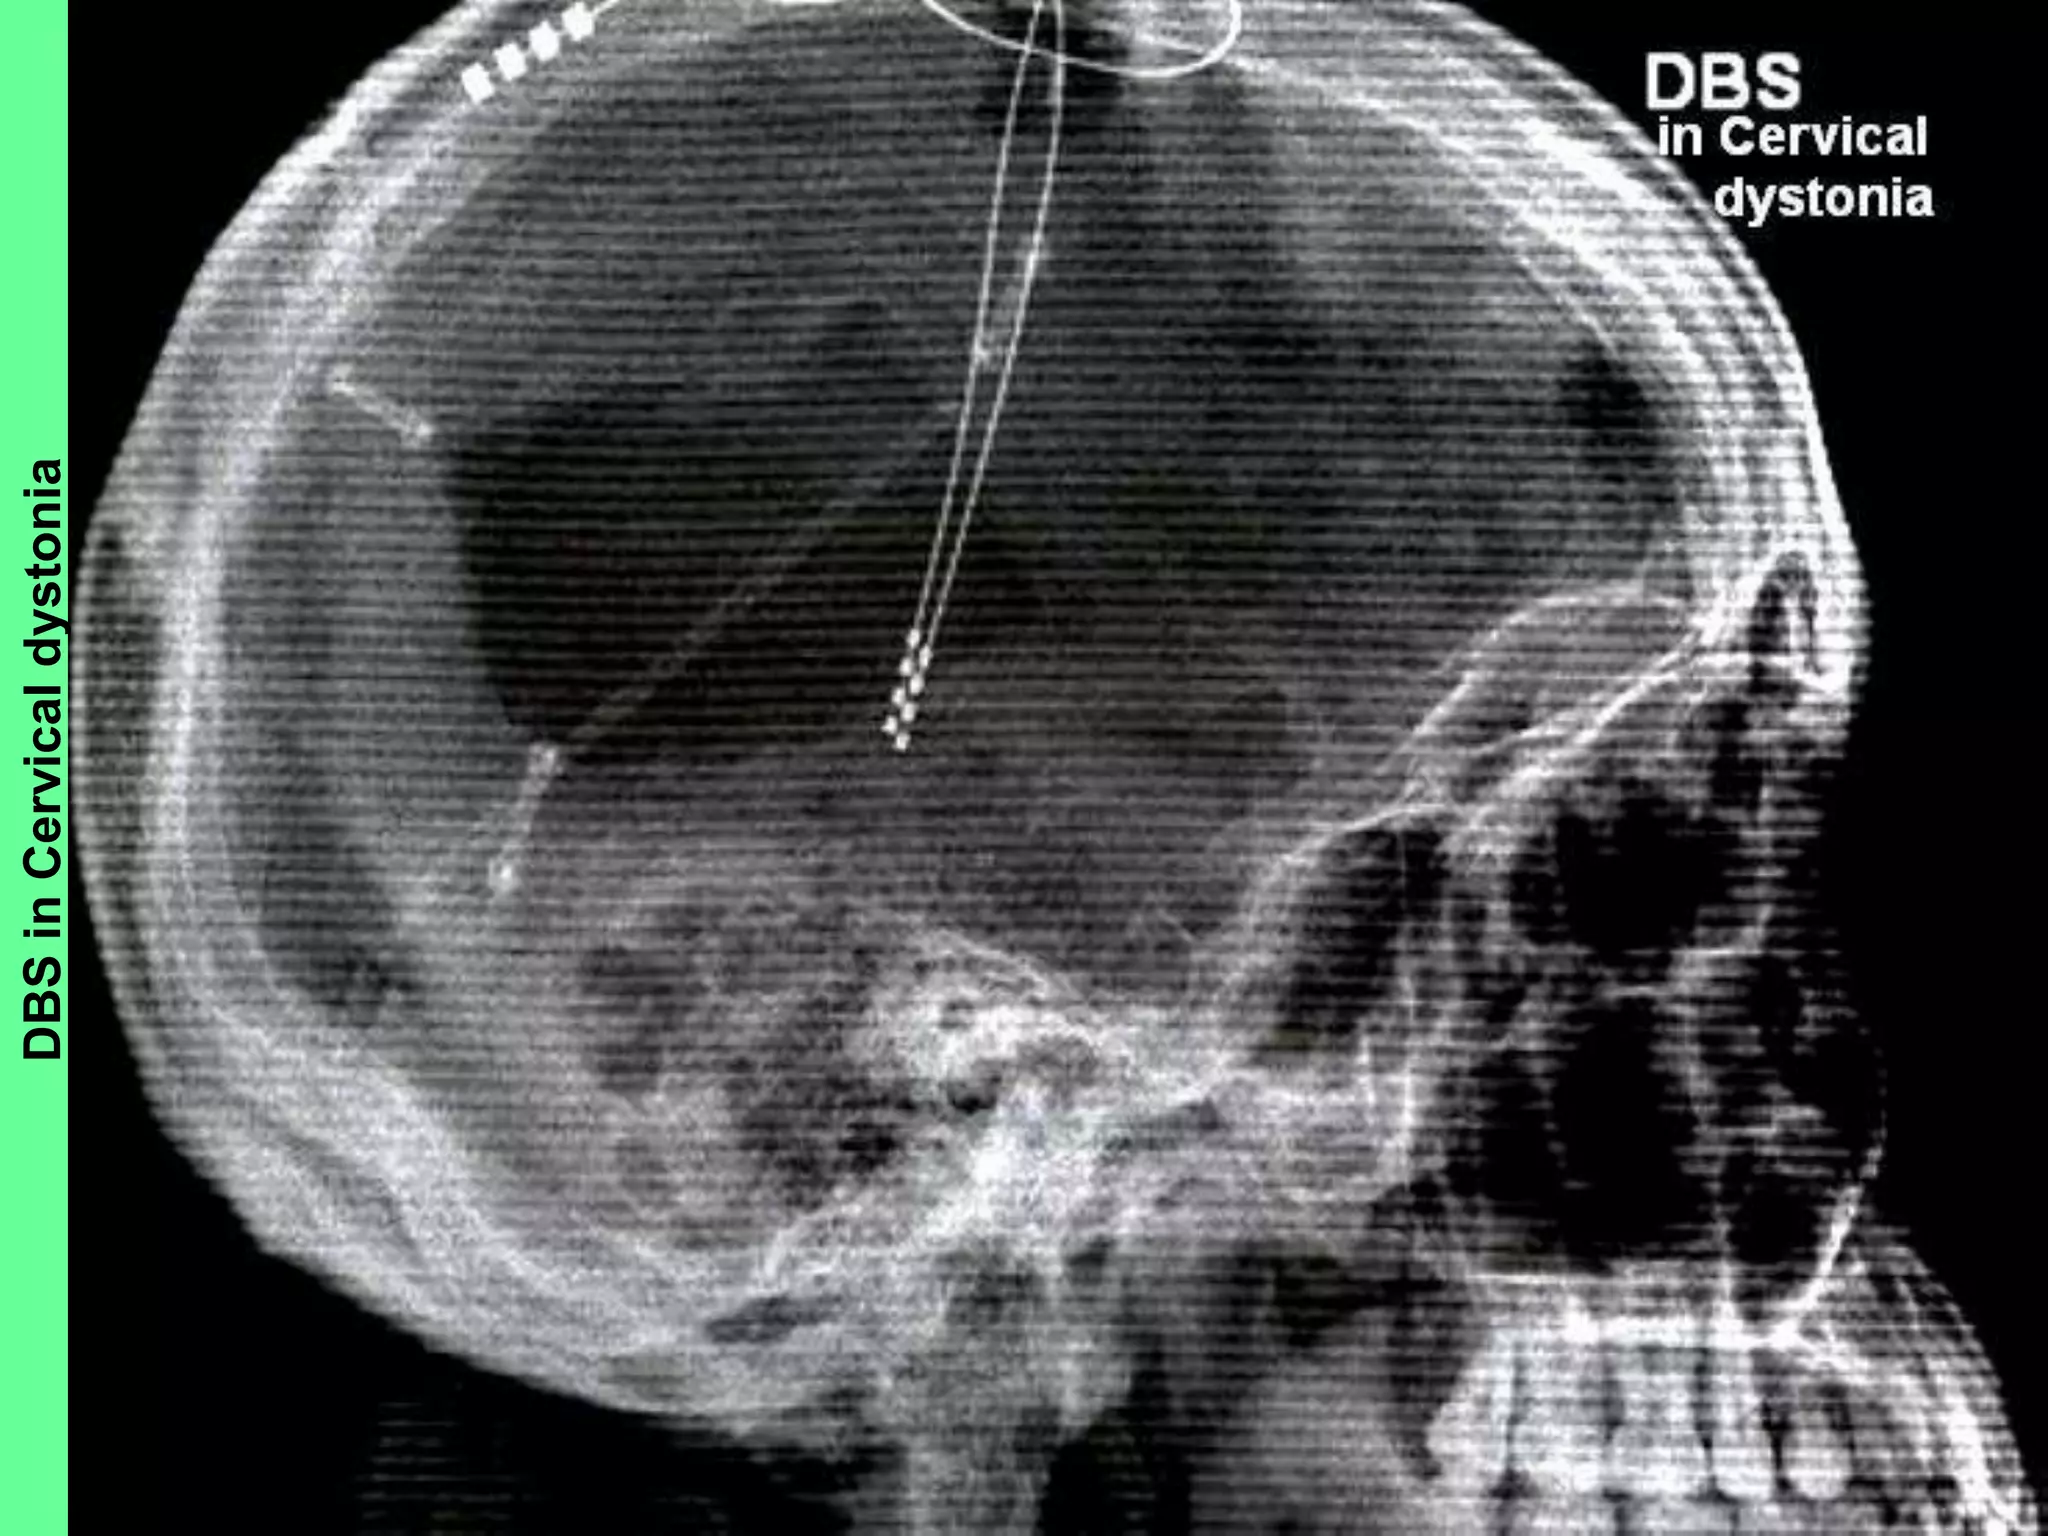

• Dystonias: Chronic, intractable (drug refractory)

Primary dystonia, including Generalized and/or

Segmental dystonia, Hemi-dystonia and Cervical

dystonia (Spasmodic torticollis) in patients >7

years; received FDA approval via Humanitarian

Device Exemption process in April 2005

DBSinCervicaldystonia